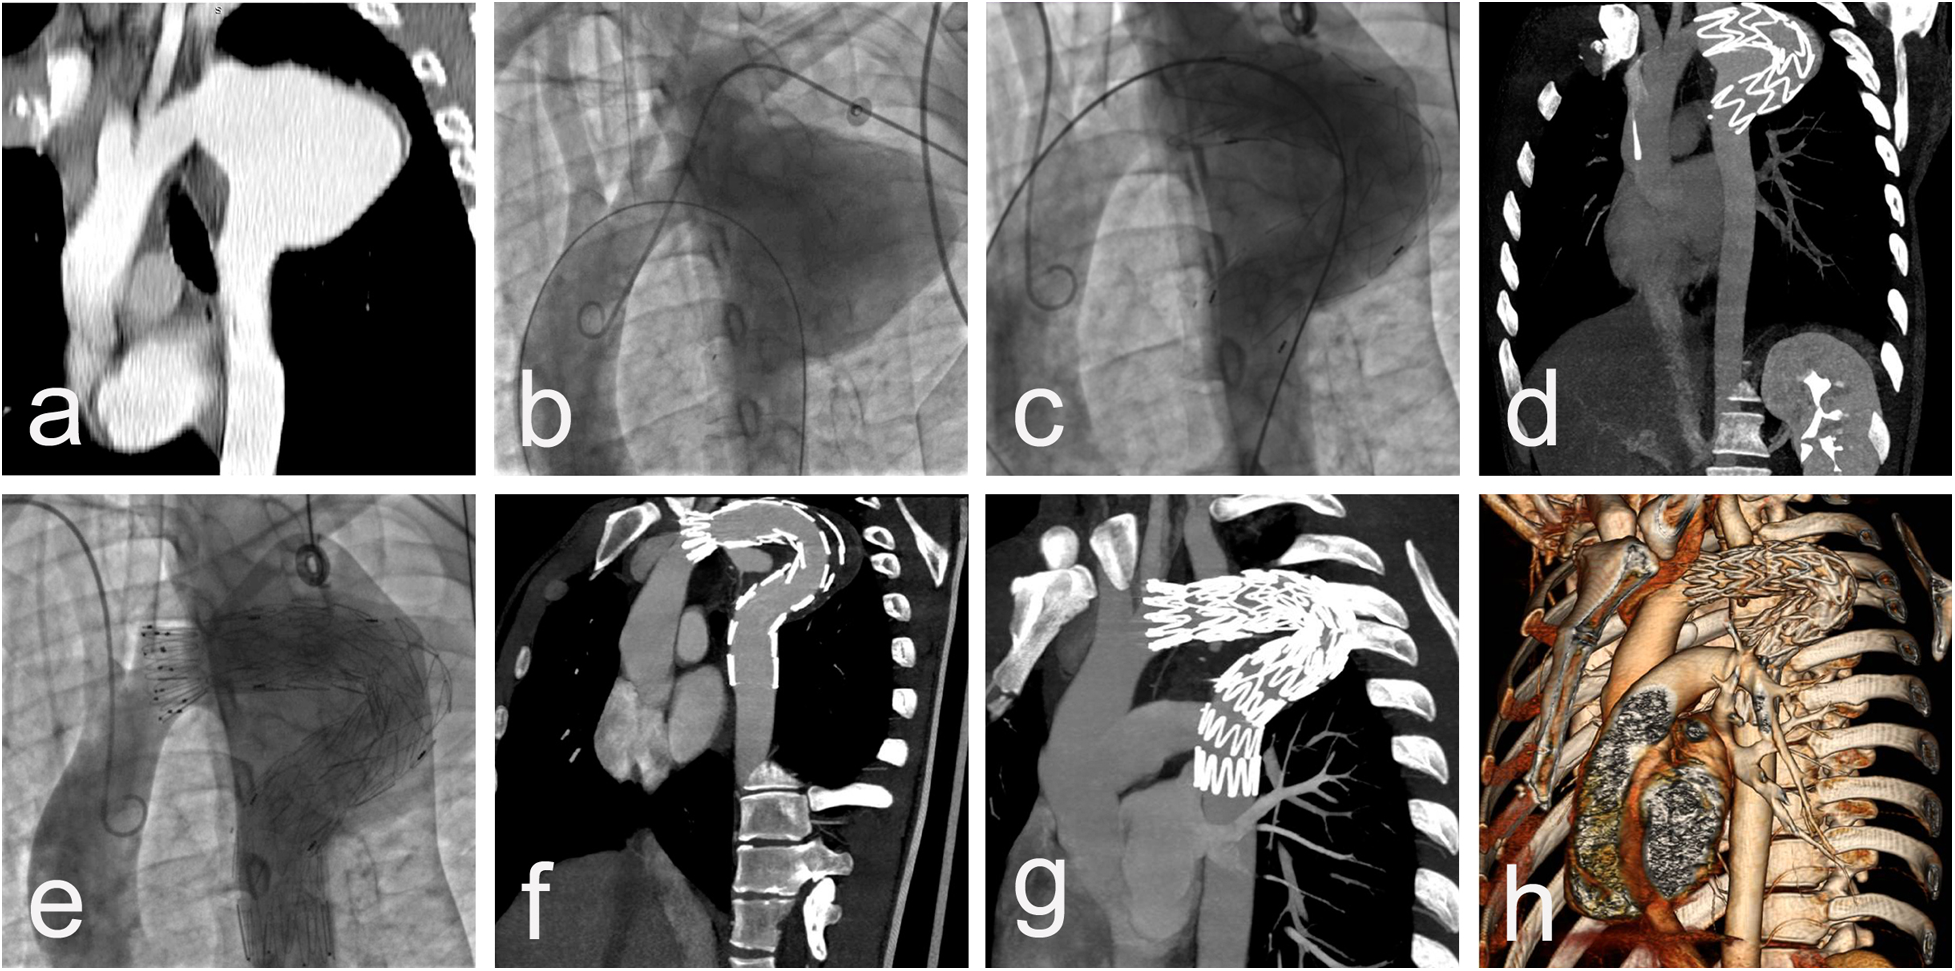

Procedural data: All cases were performed in a standard catheter lab environment. Stent-graft deployment was successful in all patients. In 5 patients, partial or complete coverage of the LSA was necessary to ensure an adequate landing zone for the endoprosthesis and to avoid endoleak. Two of them underwent aorto-carotid bypass to the left common carotid artery, performed prior to aortic stenting. No subclavian steal syndrome was observed during the hospital stay and subsequent follow-up (Figures 1a–c). Four patients required additional stent(s). Postdeployment aortography revealed type I endoleak in 4 patients, with one left under surveillance. while in the other three, additional endoprostheses were implanted to seal the leak (one received 2 additional endoprostheses, and the others received 1 endoprosthesis) with optimal results. In one of those patients, we observed a severe type I endoleak with a persistent filling of the aneurysm due to a collapse of the stent-graft (26/155 mm) in the large aneurysm, accepting its large curvature. A second endoprosthesis (28/200 mm) was positioned using two stiff guidewires to cross the old prosthesis. The additional stent-graft was positioned right behind the left carotid artery, and we achieved complete aneurysm isolation (Figures 2a–e). There was no procedural mortality and neurologic, vascular-access, or ischemic complications. All patients were cared for in the intensive care unit after the procedure, with a mean stay of 1.84 days. The average hospital stay was 9.3 days (7–19 days) (Table 3).

Figure 2

CT scan imaging (a) and aortic angiography (b) demonstrating saccular thoracic aortic aneurysm engaging LSA of 27 y/o male presenting 15 years after initial surgical repair with cough and hemoptysis. Dimensions of aneurysm 56/70 mm with no signs of thrombosis. Postdelopyment aortography revealing a collapse of the stent-graft in the large aneurysm, accepting its large curvature with severe type I endoleak (c), confirmed by immediately performed CTA, with no sign of iatrogenic rupture and preserved distal blood flow (d) Additional stent-graft positioned right behind left carotid artery and complete aneurysm isolation (e) with post-procedure CT data of completely covered LSA and small endoleak type II from large LSA (f) CT scan imaging at 1-year follow-up with complete aneurysm thrombosis, reduction of the aneurysm size with 40% and lack of endoleaks (g,h).

Follow-up: The 30-day and one-year mortality was 0%. The mean follow-up time after stent graft placement was 87 months (range, 23 to 168 months). Seven patients completed five five-years follow-ups and four-ten years follow-up. The survival rate was 80% for 3- and 5-year follow-up. According to data from the CTA performed during the follow-up period, all patients have demonstrated positive aneurysm remodeling with cavity thrombosis and size reduction. Data from the most recent follow-up scan showed that the mean aneurysm diameter had decreased to 54,9 mm (±16,6). (Figures 3a–c) Retrograde dissection from the graft, dissection beneath the implanted graft, and graft displacement were not observed. No endoleaks were diagnosed.

Figure 3

CT scan imaging showing 65 mm post-CoA repair aneurysm in a 41 y/o female, 32 years after surgery (a,b) and full cavity thrombosis with significant aneurysm shrinking to 42 mm one year after TEVAR (c).